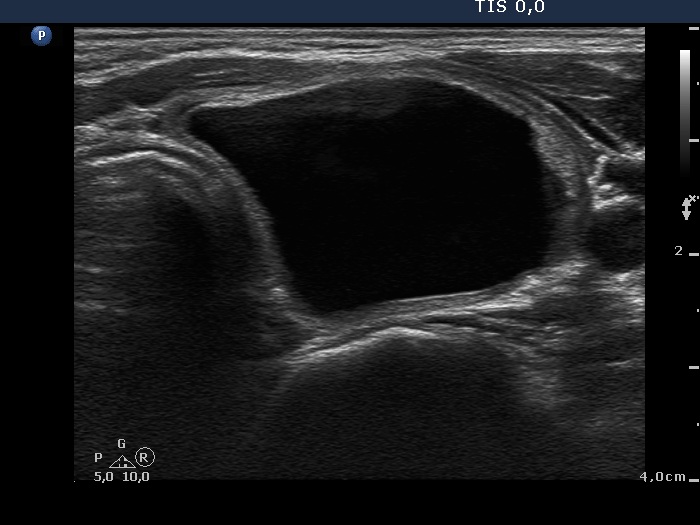

Ethanol sclerotherapy: other examples - Case 3: treatment of a gelatinous thyroid cyst

Three months prior to therapy (ultrasonographic picture 1)

Right lobe , horizontal scan. A large cystic nodule occupies almost the entire left lobe.